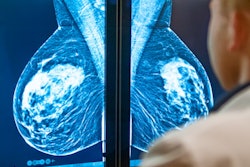

Logistical problems and personal beliefs play a key role in skipping breast cancer screening. That is the key finding of Italian researchers, who investigated why more than 30% of women miss their appointments in the northeastern region of Friuli Venezia Giulia.

The team aimed to uncover reasons behind the nonattendance of public screening via a qualitative telephone survey. In the region, 300,000 women are targeted per round for cervical screening, more than 150,000 women for breast cancer screening, and more than 300,000 men and women for colorectal cancer screening.

Friuli Venezia Giulia is the second best performing region of Italy for mammography screening, the third for colon cancer screening, and the first for cervical cancer screening in Italy, according to national figures. Nevertheless, participation levels can still be improved, the authors wrote in an article posted online in the journal Public Health on 17 January.